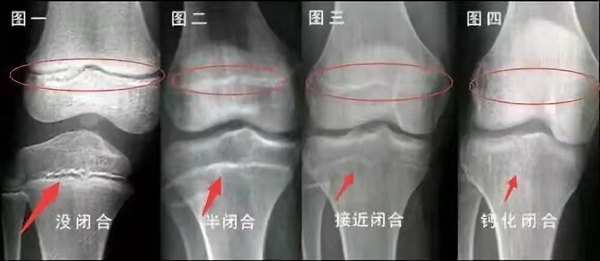

未成年時(shí)隨著年齡的增加骺軟骨端不斷骨化,骨骼就不斷增長。當(dāng)骨骺線完全閉合時(shí)骨骼就停止生長,個子也就不再增長了。一般骨骺端完全閉合的年齡是18~20歲左右。

青少年一般什么時(shí)候骨骺閉合?

一般女孩是在16歲,男孩是在18歲。

一般來說,女孩的骨齡超過14歲,男孩的骨齡超過16歲,這時(shí)其骨骺線已接近閉合,基本沒有長高的機(jī)會了。

因此,越早了解骨骺線閉合情況,越早干預(yù),孩子長高的可能性越大。